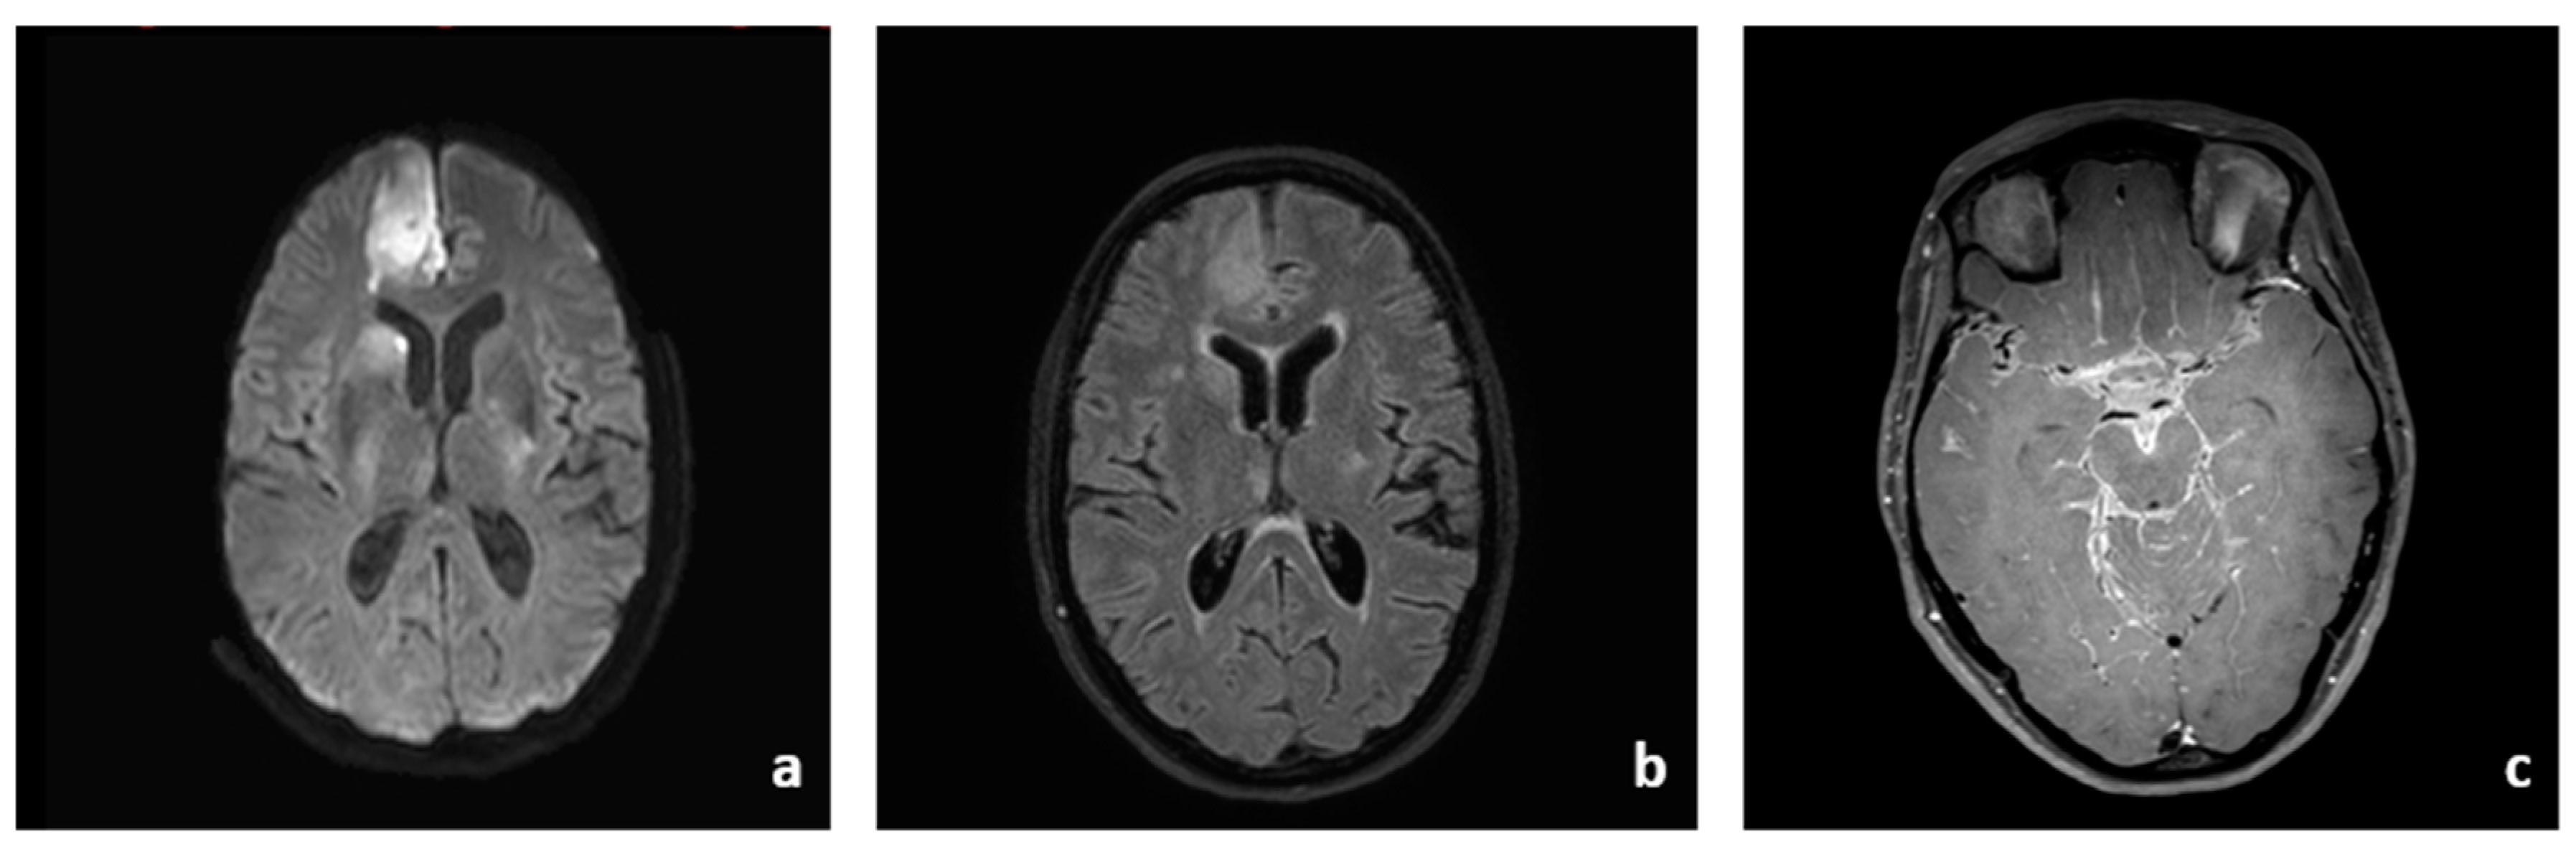

The patient’s neurological symptoms worsened six hours post-intervention with aggravated hemiparesis of the left side. An immediate MRI scan showed a circumscribed intracerebral hemorrhage in the right temporal lobe and a large new subdural hematoma on the right hemisphere with a midline shift to the left and incipient subfalcine and uncal herniation (Figure 3d). The eptifibatid therapy was discontinued and the patient was directly taken to neurosurgery for hemicraniectomy (Figure 3e).

The patient’s MRI and CT images obtained in the following days showed successful evacuation of the SDH, but progressive infarcts in the right MCA territory and bilaterally in the ACA territories (Figure 3f). The implanted stent was patent at all times under platelet inhibition with ASA only.

Figure 3. Follow-up imaging with DSA-series, MRI and CT imaging. DSA-series showing successful stent implantation in the right MCA with improved vessel diameter/perfusion (ac). MRI and CT imaging demonstrating late-onset complications with severe infarct demarcation in both hemispheres and right hemispheric intracerebral hemorrhage as well as subdural hematoma requiring neurosurgical intervention and hemicraniectomy (df).